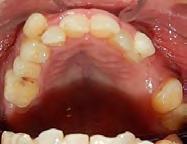

Estudios intraorales de inicio

En las fotografías ( Figura 2 ) se observa clase III esquelética, hiperdivergente, la clase III molar derecha y clase que no está determinada, la molar izquierda, clase canina derecha III, clase II canina izquierda, (Figura 3) con la ausencia de los OD 17, 15, 16, 36, 37, 47, el 23 está retenido en palatino, el overjet y overbite están disminuidos, con la línea media inferior desviada, la paciente refiere que ya le habían realizado una cirugía de Lefort IV antes de llegar al CESO.

Vista oclusal las formas de arco oval superior es indeterminada al igual que la superior e inferior (Figura 4)

Figura 2. Frente inicio. Figura 3. Izquierda y derecha intraoral de inicio.

se ve la malposición, apiñamiento con la ausencia de órganos dentarios.